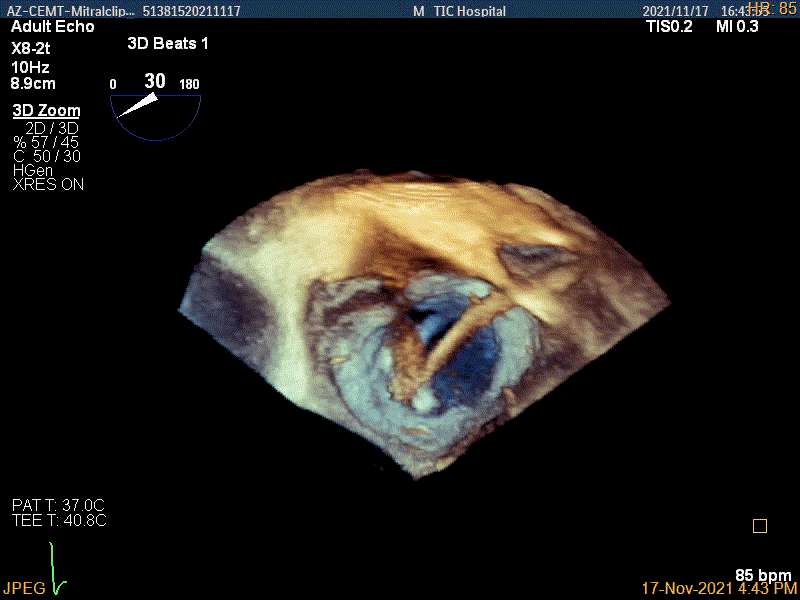

3D-color MV view:源自于交界区的大量反流

3D视图下进夹子并建立trajectory

3D视图打开夹子

3Dcolor证实残余分流主要来源于残余脱垂

3D视图两个夹子近似并排排列

3D-color视图下两个夹子间少量残余反流